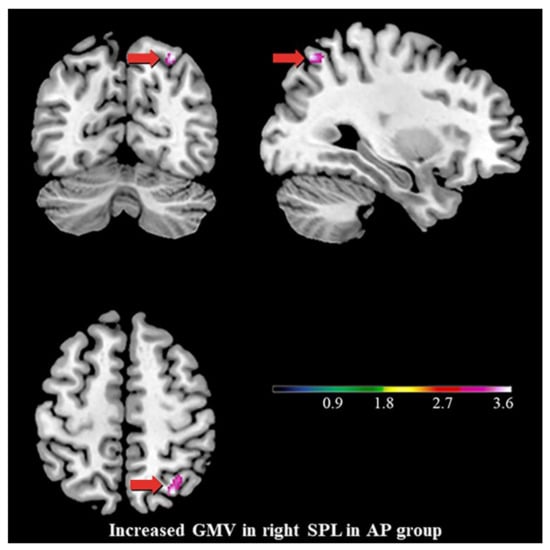

4.2. Increased GMV of the Right SPL, the Stigmata of Childhood AP?